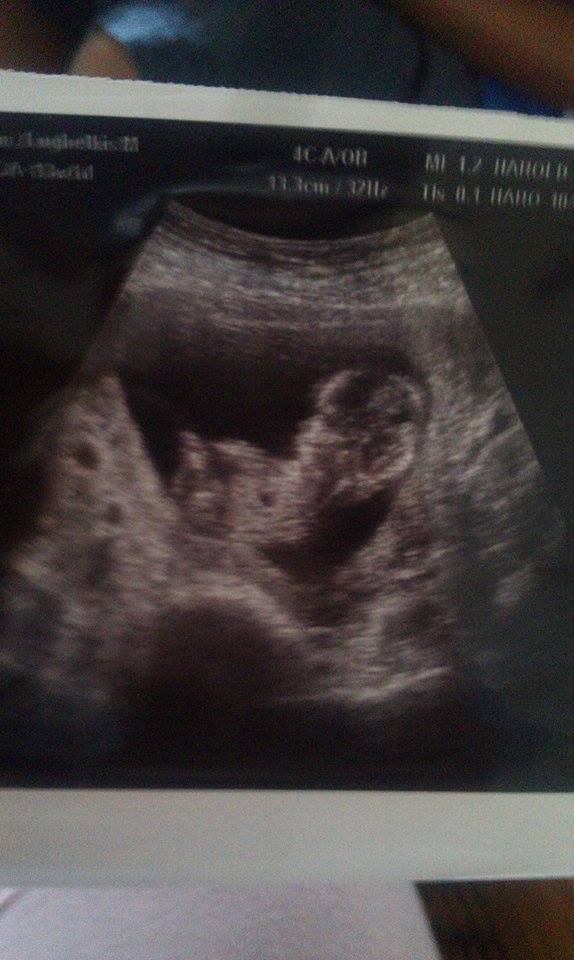

Third picture: Attachment 21436 I think that might be the part of the leg because in the video it was first the leg and then part of the leg dissapeared and that stayed and then it blended again with the leg. I think baby's torso is a little longer too so parts might be missing in the pic. Or is that the nub????